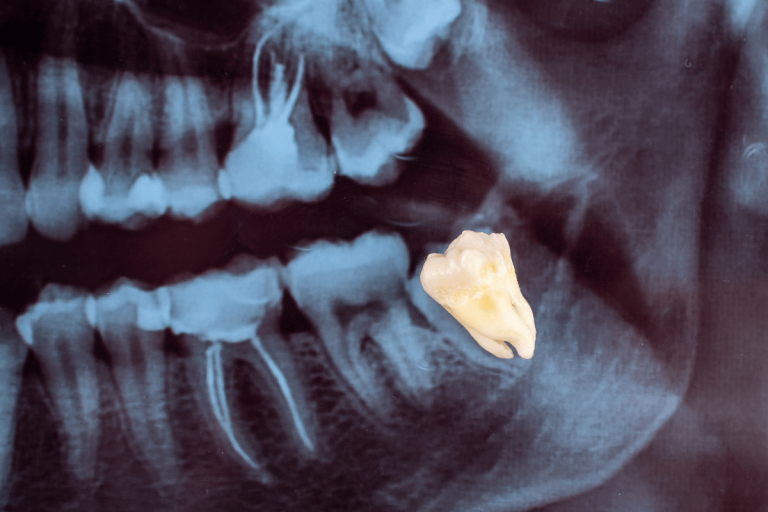

Мъдреците са третите кътници, които израстват в устната кухина между 17-та и 24-та година (т.н. години на мъдростта). Мъдреците са 4 на брой – по 2 на горна и долна челюст, но могат да бъдат и по-малко или изобщо да не израснат. Мъдреците са полезни за дъвкателната функция ако са израснали правилно и човек има достатъчно място в устата за тях. Когато обаче мястото е недостатъчно или са израснали по неправилен начин могат да предизвикат болка, кариеси и заболявания на венците.

Израснали са неправилно или са останали блокирани в челюстта;

Израстват под ъгъл спрямо другите зъби, което може сериозно да повреди съседните зъби;

Образуване на кисти (мехурчета пълни с течност), които могат да унищожат костта и да предизвикат загуба на зъб;